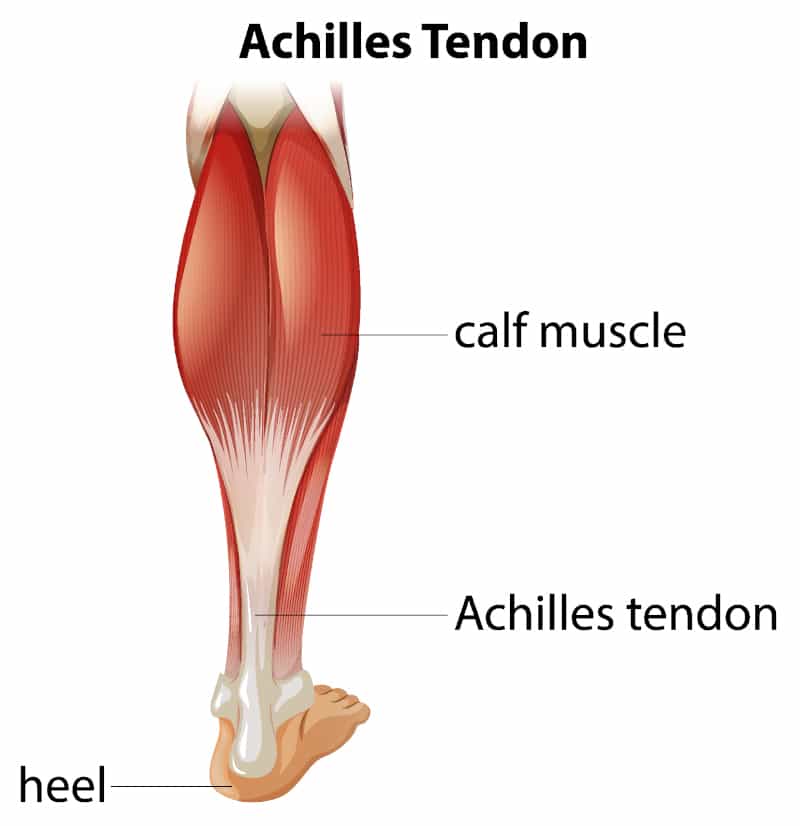

pictures of achilles tendon

Achilles Tendon – Squat University

Achilles Tendon – NJSM

Achilles Tendon Diagram – 1000+ images about medical anatomy on …

Achilles Tendon | Achilles tendonitis, Achilles, Achilles tendonitis …